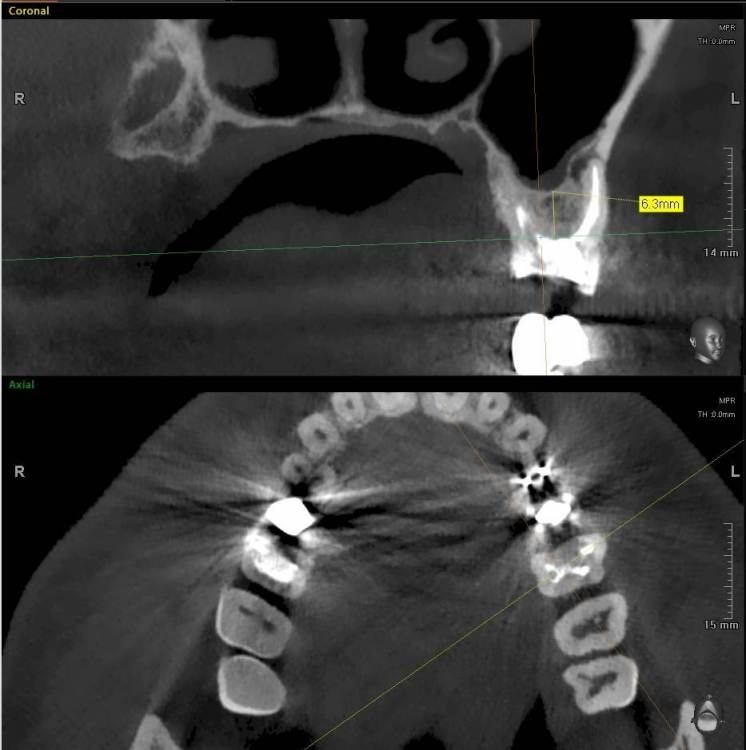

ict Опубликовано 18 января, 2023 Поделиться Опубликовано 18 января, 2023 зуб 2.6, в канале стекловолоконный штифт. Что лучше делать - вынимать штифт, перепломбировать каналы и на вкладку коронку или выдернуть зуб и имплант? Кость не очень высокая - какие могут быть проблемы с установкой импланта? Достаточно ли будет подсыпать костного материала или что-то сложное - открытый синуслифтинг? Ссылка на комментарий

ict Опубликовано 20 января, 2023 Автор Поделиться Опубликовано 20 января, 2023 (изменено) Большое Спасибо! Решил удалить, как заживет поменять пломбу на 2.7 (Вы абсолютно точно определили проблему с 2.7) и потом имплант. Склонился к удалению потому, что стоимость перелечивания сравнима с имплантом и вероятность успешного перелечивания без микроскопа невысока. В корне с гранулемой два канала, дополнительный с собственным отверстием (выщерблина на верхушке) без рентгеноконтрастного материала, вероятно не запломбирован. Пломба на 2.6 скололась месяца 3 назад скорее всего стала подтекать в канал, гранулема подросла, чувствительность в щеке уменьшилась (канал нерва над верхушкой виден). Будет обидно, если гранулема не уйдет Изменено 20 января, 2023 пользователем ict Ссылка на комментарий